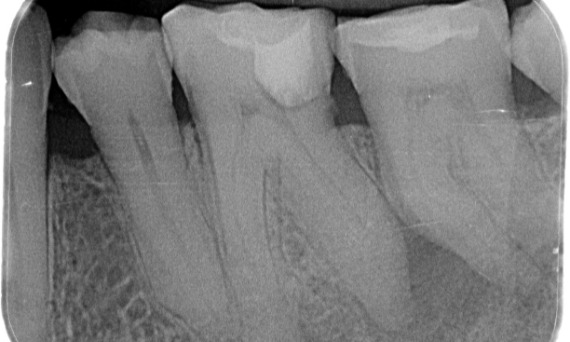

« J’ai choisi TruNatomy pour pouvoir préserver autant de dentine que possible afin de surmonter le défi lié à la charge occlusale et d’augmenter la longévité de la dent. » - Dr Abuelezz

Avant : L’examen a révélé une lésion carieuse liée à la première molaire mandibulaire droite. L’examen radiographique a révélé la proximité de la lésion avec la corne pulpaire et, en l’associant à la plainte principale, un diagnostic final de pulpite chronique irréversible a été posé.

Après : La cavité d’accès a été réalisée de la manière la plus conservatrice possible. TruNatomy a été le système de choix en raison de l’âge du jeune patient. Nous devions préserver la dentine autant que possible afin d’augmenter la capacité de la dent à surmonter la charge occlusale et d’accroître la longévité de la restauration finale.